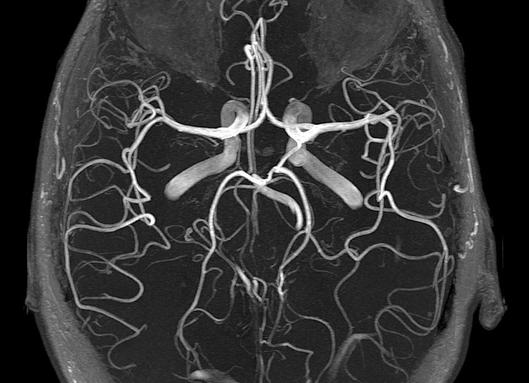

МРТ тонкого и толстого кишечника. Гидро МРТ. Колоноскопия

Существует множество эффективных и достоверных методов выявления патологий желудочно-кишечного тракта. Самыми информативными считаются гидро МРТ, колоноскопия и ирригоскопия, о которых и пойдет речь.